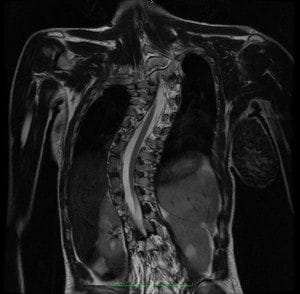

Fig. 5.- Magnetic Nuclear Resonance (MRI) with the coronal section of the spine in case of idiopathic scoliosis. Here, the spinal canal can be seen with the spinal cord going from convexity to convexity inside the vertebral canal, indicating the existence of an important caudal force caused by the cord traction.

Idiopathic scoliosis is the result of an avoidance or compensation mechanism of the spine’s reaction to the caudal cord traction, produced by a tense Filum Terminale. This traction force is not evident in the complementary tests such as MRIs.